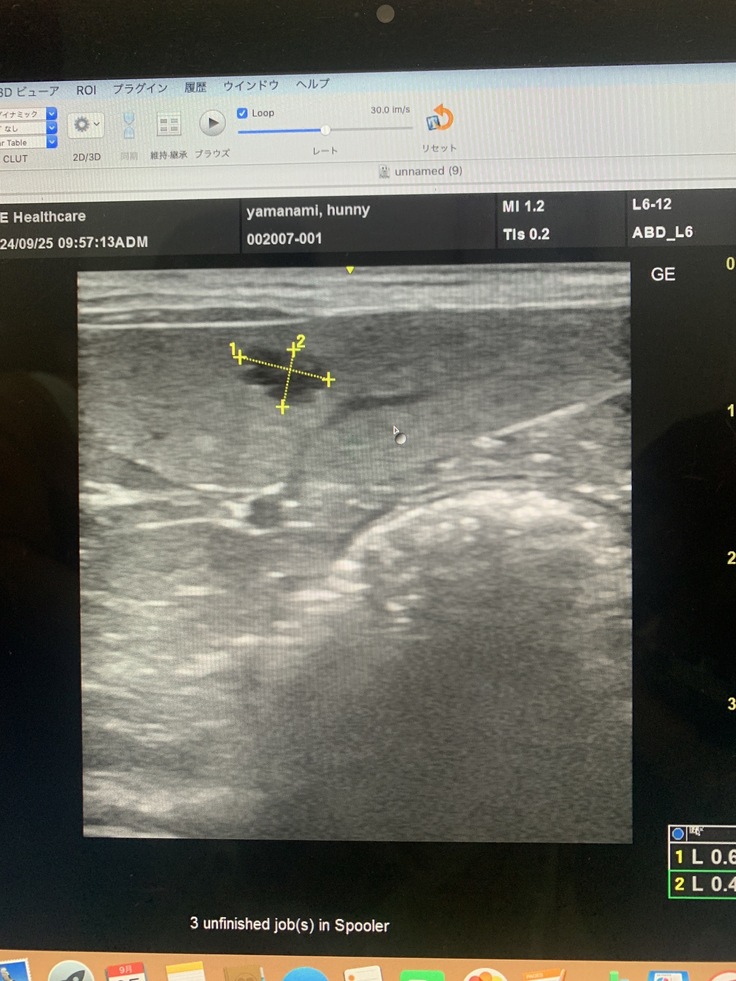

9月25日かかりつけ受診と脾臓の転移見つかる

脾臓にしこり、影→1センチ4ヶ所が見つかった

脾臓摘出が一般的

ハニーの今の体調だと外科手術難しい

細胞診も脾臓に針刺したら脾臓破裂し出血多量で亡くなる

おそらく、脾臓の腫瘍も転移したものの可能性が高い…